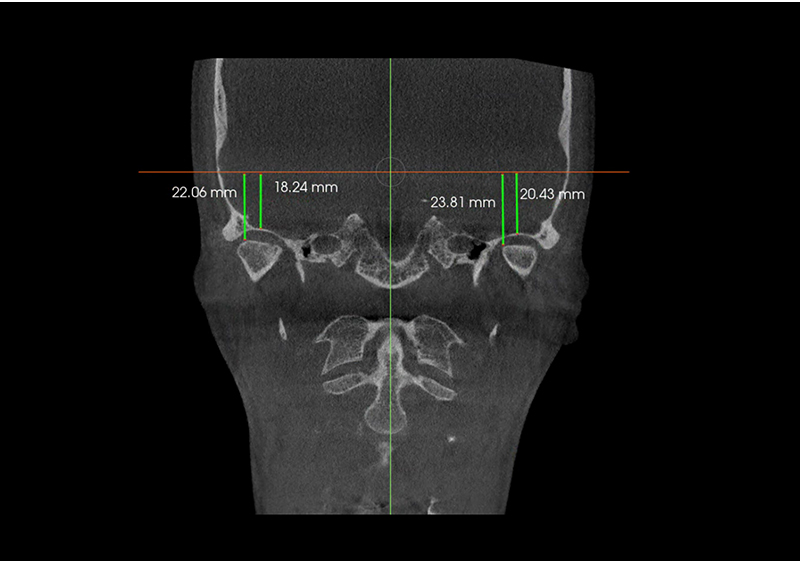

Estudio de Simetría

Nos permite analizar las distintas estructuras craneofaciales y su

relación entre si, para determinar biotipos faciales y predecir líneas de

crecimiento y desarrollo, además de posibles compensaciones